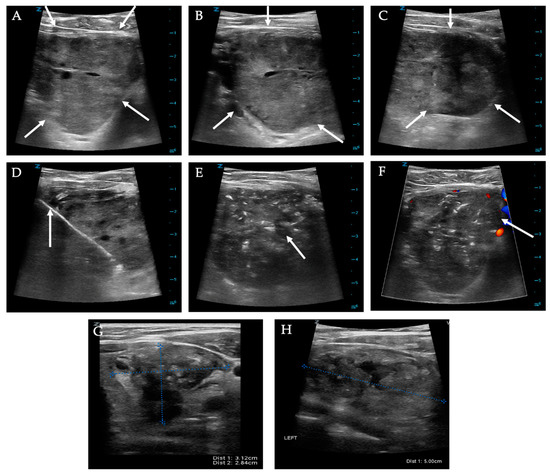

2.1. Ultrasound